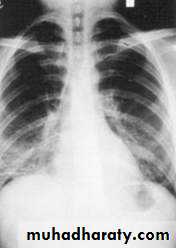

Miliary TB